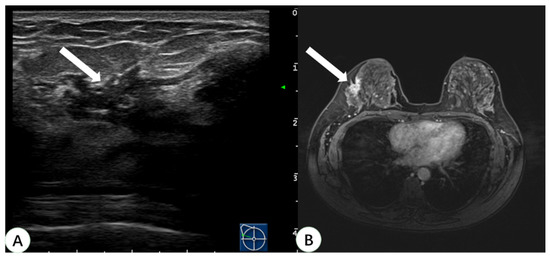

Figure 5.

A 44-year-old woman with dense breast tissue underwent virtual navigation: (A) Real-time US with virtual navigation revealed the corresponding lesion (arrow) in the right breast at the 10-o’clock position 5 cm from the nipple, which underwent ultrasound-guided biopsy; (B) CE-MRI showed a non-mass enhanced lesion (arrow) in the upper outer right breast, undetected on second-look US. Pathology obtained by ultrasound-guided biopsy with virtual navigation demonstrated sclerosing adenopathy with intraductal papilloma formation. US = ultrasound; CE-MRI = contrast-enhanced magnetic resonance imaging.